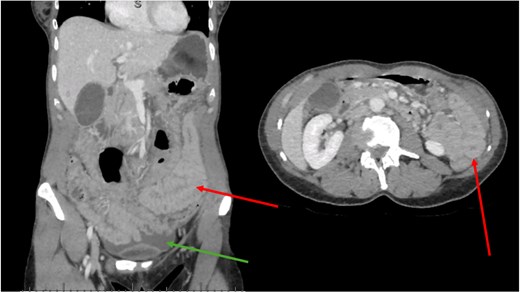

An abdominal CT scan with intravenous contrast (Fig. 1) demonstrated abdominal free fluid without pneumoperitoneum, associated with diffuse thickening of small bowel walls and extra-hepatic bile duct dilatation. All vascular mesenteric axes were permeable.

CT scan. Green arrow shows free fluid. Red arrows show diffusely thickened bowel wall.